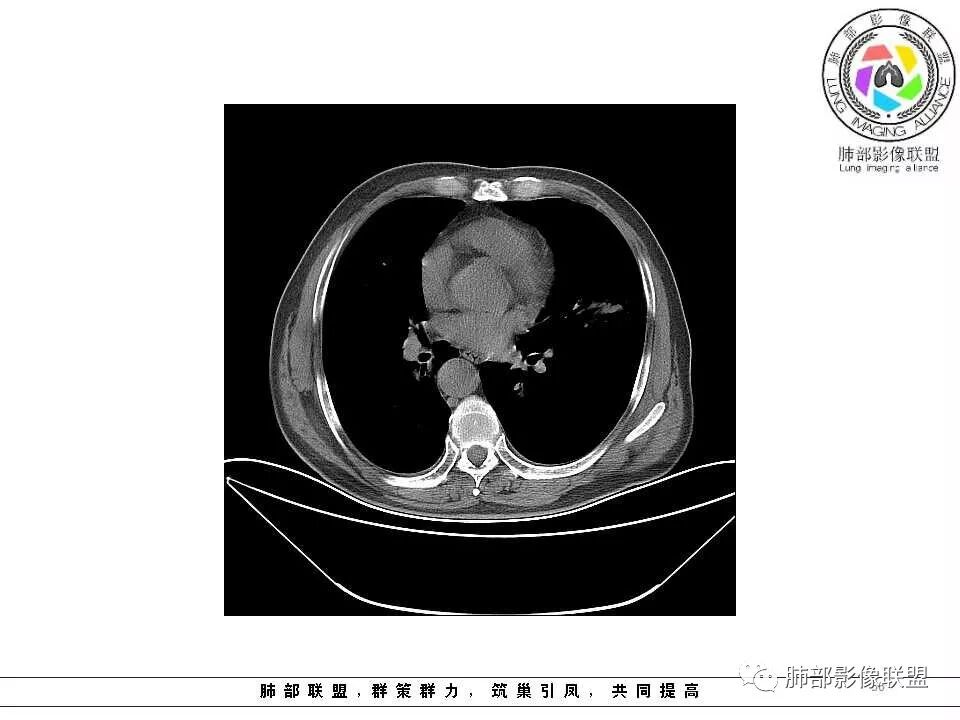

老年男性,肺气肿基础。约一年时间出现左肺上叶舌段支气管近端结节影,远端斑片样阴影,边缘模糊。考虑近端恶性占位,远端有阻塞性炎症。

老年男性,有咳血病史,左肺上叶舌段一年时间出现新发类圆形小结节,感觉在支气管内,部分凸出气管外,没有mpr不好说,远端肺野斑片模糊影,考虑阻塞性炎症,纵隔无明显肿大淋巴结,小细胞代排,按照发展速度,类癌低度恶性,应该发展缓慢,一年病史,代排,首先考虑鳞癌并阻塞性炎症

左肺上叶舌段支气管管壁略增厚 间隔一年 管壁增厚明显 向腔外突出形成结节 管腔闭塞 远端片状及斑片影 纵隔淋巴结增大 肺气肿背景 考虑鳞癌伴阻塞性炎症可能

老年男性,咯血1月,肺气肿背景,16年左肺上叶舌段结节,左肺门疑似淋巴结肿大,呈结节感。17年左肺上叶舌段见沿支气管走行分布结节 远端阻塞性肺炎,左肺门淋巴结肿大明显,首先考虑恶性病变,鳞癌?类癌?

老年男性,肺气肿背景,左肺上叶舌段一年前小结节后长大,实性,与邻近气管关系密切,远端有少许小片状炎症类小结节状,左肺门淋巴结肿大,首先考虑恶性,鳞癌可能性大,代排小细胞癌。病灶下方斑片状影,考虑炎症。

老年男性,咯血1月,肺气肿背景,左肺上叶舌段见沿支气管走行分布结节,呈葫芦样改变,左肺门淋巴结肿大明显,首先考虑恶性病变,小细胞癌可能